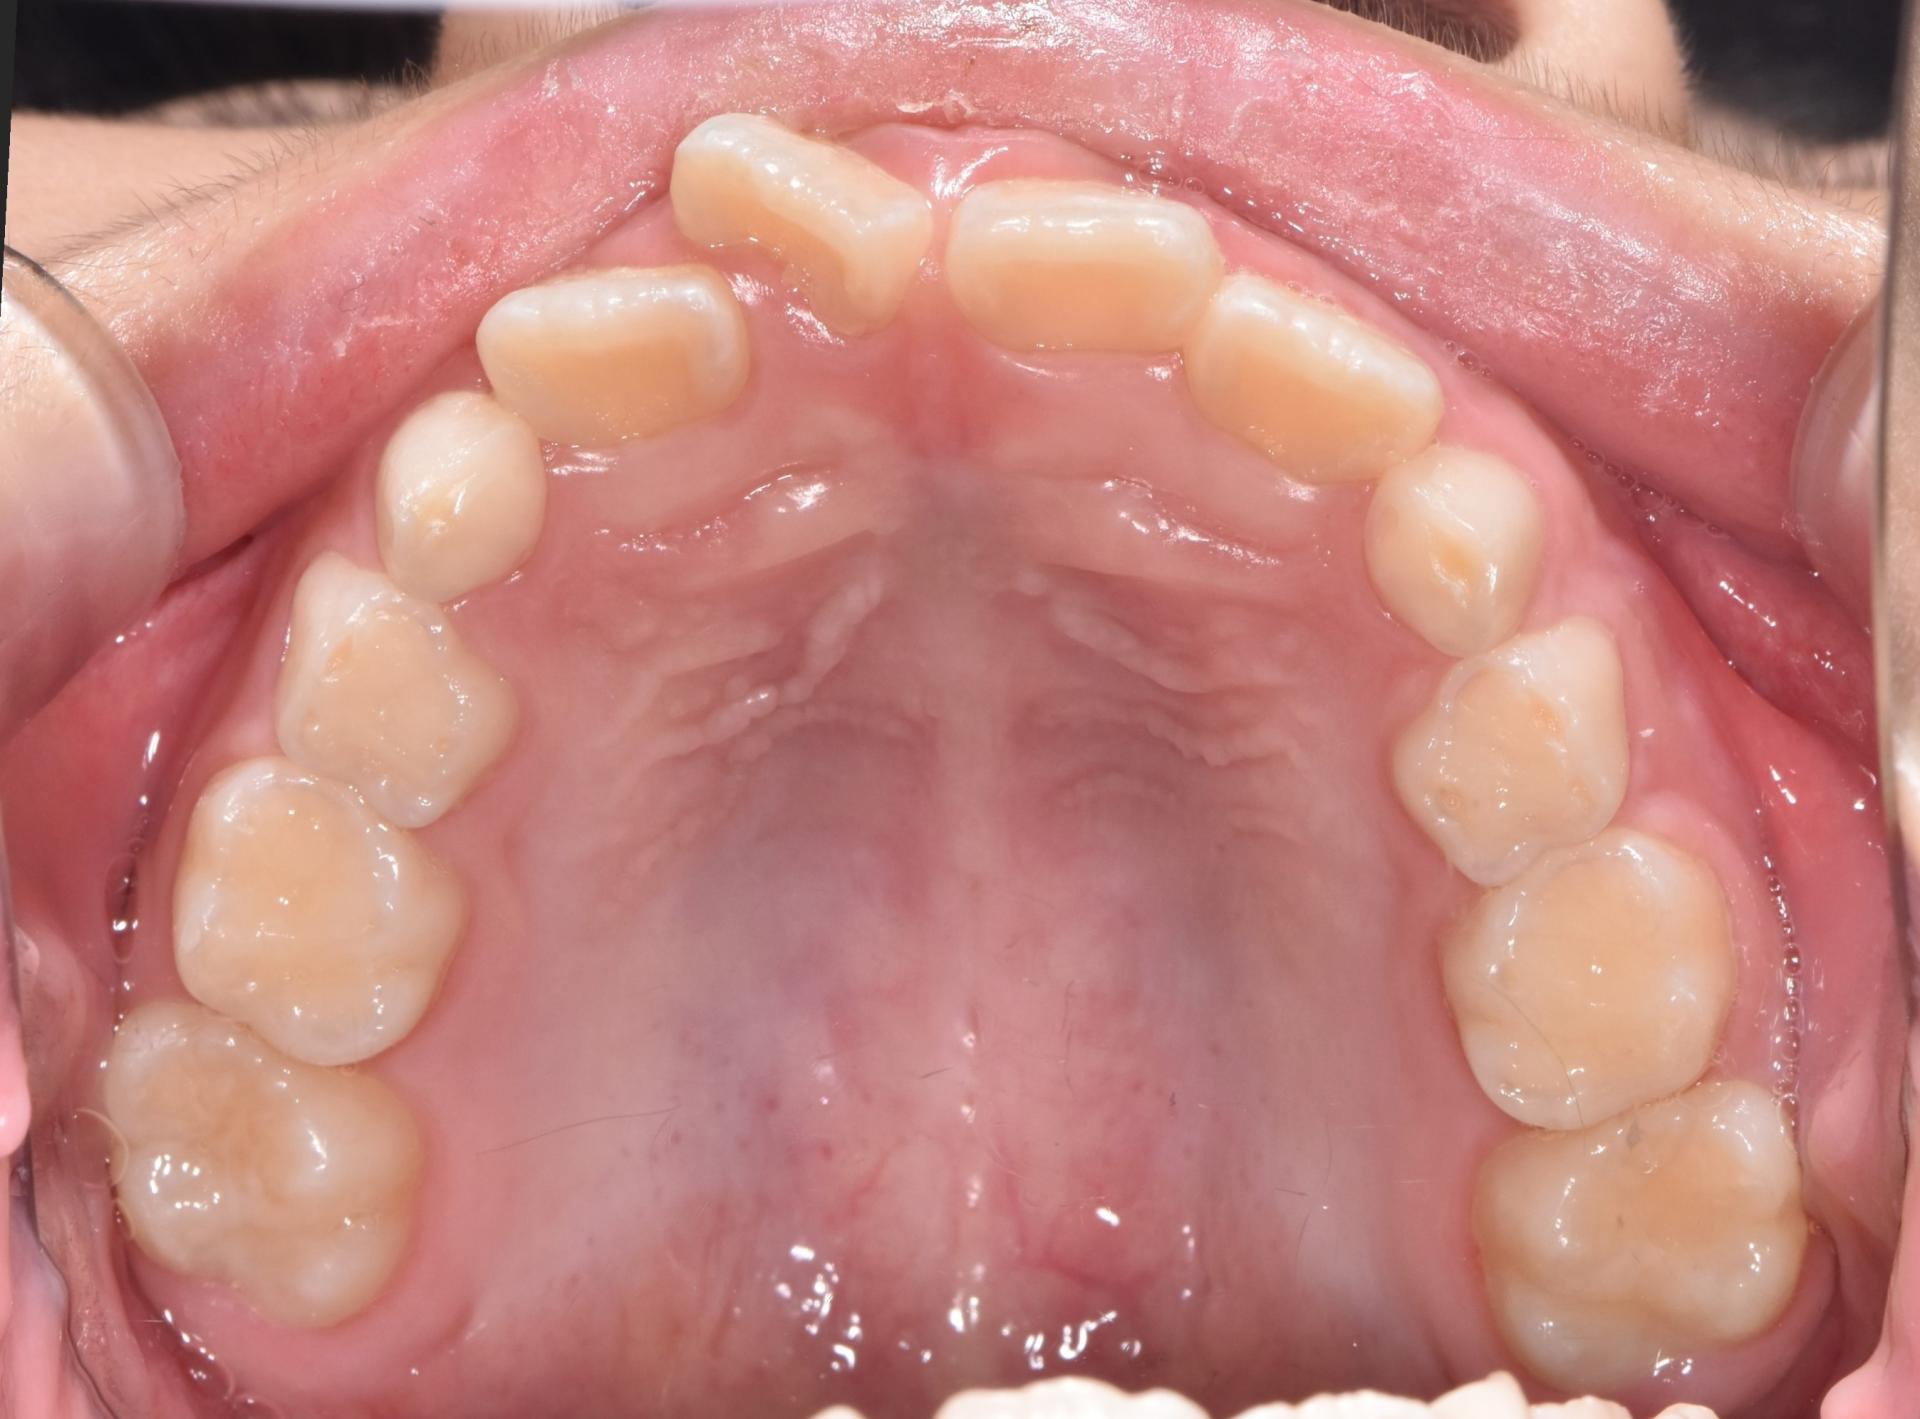

예전부터 많이 하던 교정으로, 악궁확장장치(뺐다꼈다 하는 장치)로 악궁을 넓혀 공간을 만들고 삐뚤빼뚤한 치아는 브라켓 철사교정으로 예쁘게 해주었습니다.

치료완료 후의 모습입니다. 앞니도 가지런해졌고, 좁았던 악궁이 넓어져서 추후 나올 송곳니, 어금니의 공간도 충분합니다.

치료개시일 : 2024.02.16. 치료종료일 : 2024.09.09. |

치료개시일 : 2024.02.16.

치료종료일 : 2024.09.09.